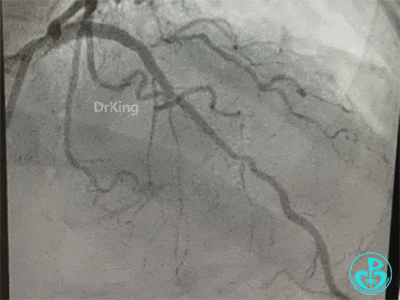

左主干分叉病变采取Crush双支架术式,回旋支开口植入支架,前降支开口球囊挤压后左主干到前降支植入支架(Crush双支架术式)。

导丝准备穿支架网眼Rewire回旋支时患者血压继续下降。去甲肾上腺素微量泵剂量逐渐增大至25ml/h,立即置入IABP,血压回升后再继续操作。

导丝Rewire回旋支,非顺应性球囊分别后扩张前降支和回旋支支架,对吻扩张。

患者术中血压偏低,一度出现烦躁。及时IABP置入是手术能顺利完成的保障。术前的准备很全面,造影结果如下。